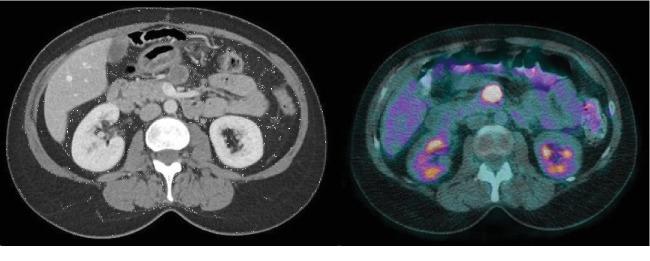

Primary colorectal leiomyosarcoma is an excessively rare entity. It is associated with an aggressive behavior and typically favor hematogenous spread. The current standard of care is surgical resection. A 49-year-old patient presented with a 2-month history of fever. A PET-scan revealed a hypermetabolic mass in the transverse colon, and colonoscopy confirmed a tumor. A right hemicolectomy was performed. Histopathological diagnosis was of a leiomyosarcoma. Fourteen months after the surgery, a follow-up abdominal scan revealed a 2 cm mesenteric lymph node that was hypermetabolic on PET-scan. The mesenteric lymph node was resected and histopathology confirmed a leiomyosarcoma metastasis. This case opens the controversy on the management of rare lymph node recurrences in colorectal leiomyosarcoma.

原发性结直肠平滑肌肉瘤是一种极其罕见的疾病。它具有侵袭性,通常倾向于血行转移。目前的标准治疗方法是手术切除。一名49岁患者有2个月的发热病史。PET扫描显示横结肠有一个高代谢肿块,结肠镜检查证实为肿瘤。进行了右半结肠切除术。组织病理学诊断为平滑肌肉瘤。手术后14个月,腹部随访扫描显示一个2厘米的肠系膜淋巴结,PET扫描显示其代谢活跃。切除该肠系膜淋巴结,组织病理学证实为平滑肌肉瘤转移。该病例引发了关于结直肠平滑肌肉瘤罕见淋巴结复发治疗的争议。